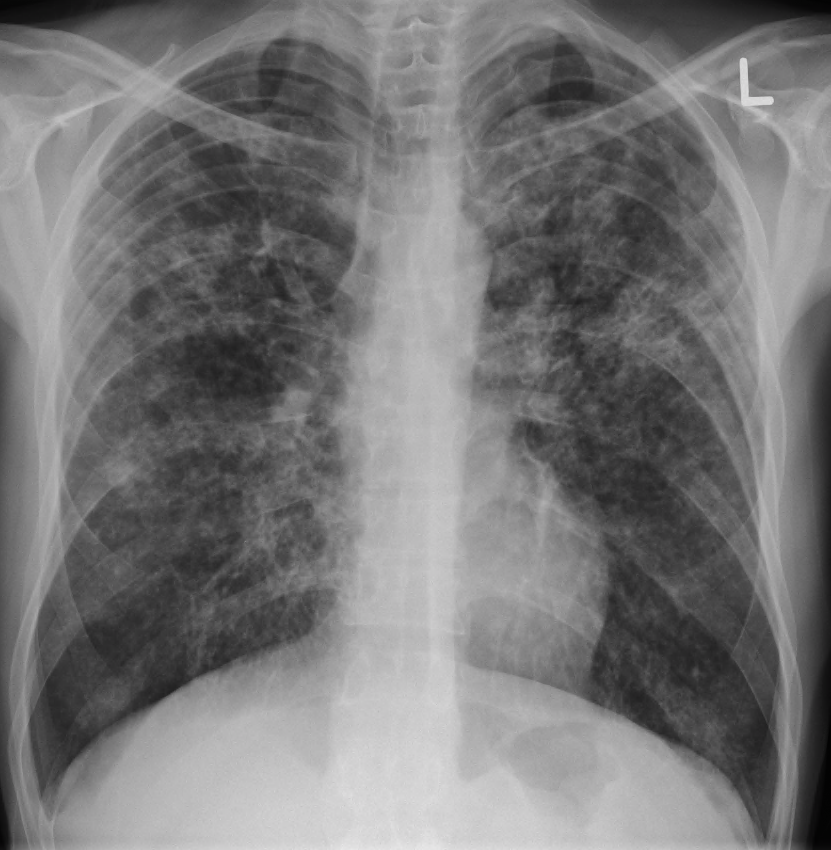

13 Bacteria ในข้อใด สัมพันธ์กับ Pseudomembranous colitis ที่เกิดจากการให้ Antibiotics นานๆ

30 ชาย 45 ปี ไข้ ไอ เสมหะ หอบเหนื่อย นำ sputum นำไปย้อม AFB : พบ red bead-like organism ส่ง CXR ได้ดังรูป จงบอกชื่อ organism ก่อโรค เป็นชื่อวิทยาศาสตร์